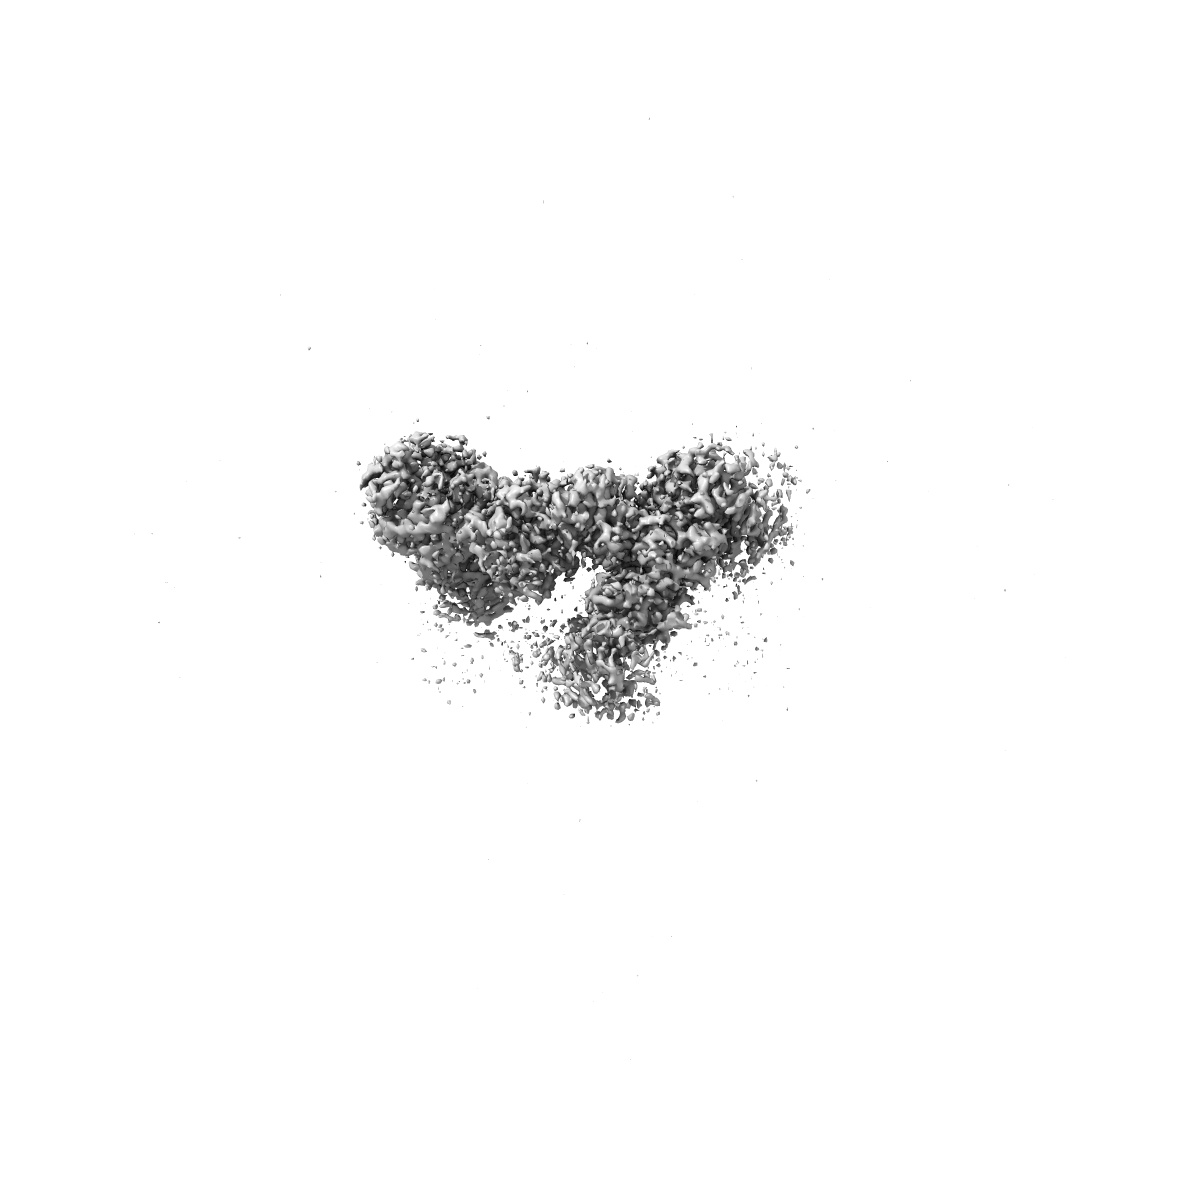

Structure of C-terminal half of LRRK2 bound to GZD-824

EMD-41756

Single-particle

2.9 Å

Sample Organism: Homo sapiens

Sample: Complex of LRRK2-RCKW with GZD-824

Fitted models: 8tze

Deposition Authors: Villagran-Suarez A, Sanz-Murillo M, Alegrio-Louro J, Leschziner A

Inhibition of Parkinson's disease-related LRRK2 by type I and type II kinase inhibitors: Activity and structures.

Sanz Murillo M , Villagran Suarez A , Dederer V , Chatterjee D, Alegrio Louro J , Knapp S , Mathea S , Leschziner AE

(2023) Sci Adv , 9 , eadk6191 - eadk6191